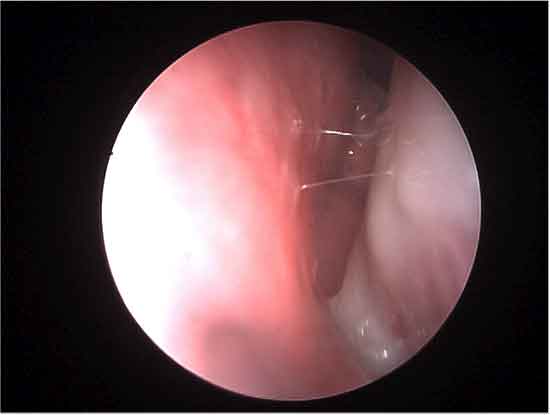

Dacriocistorinostomia Endoscopica: utilizzo della Transilluminazione